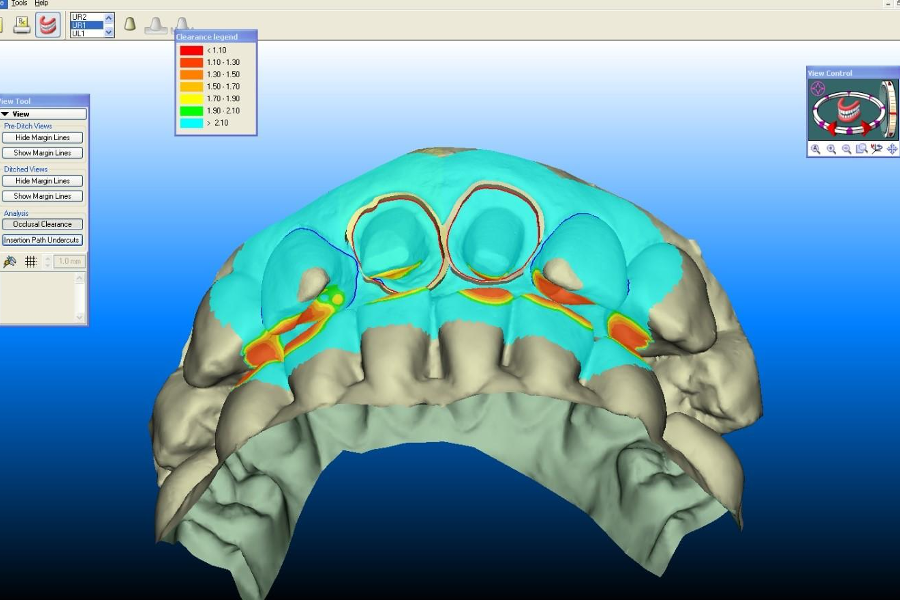

Well, initially it was as simple as looking at your preparation on a large monitor.

I was quite happy with my prep. That was until I saw it on the monitor at 60x magnification and then I had to effectively re-prep it as you can’t unsee that sh*t!

So not only did the Itero improve my preparations, but it also led to me getting better loupes.

It allowed for ‘impression-making’ rather than ‘impression-taking’. This is because it was so much easier to add more information if needed. Whereas with a conventional impression, you just get what you get and adding more detail is usually impossible.

Another advantage was somewhat unexpected. The models were amazing!

The little articulator that came with them, even though simple, just seemed to work. Rob and Ashley (my technicians) just loved them.

Not to mention the bites seemed better. As did the contacts and the fits.